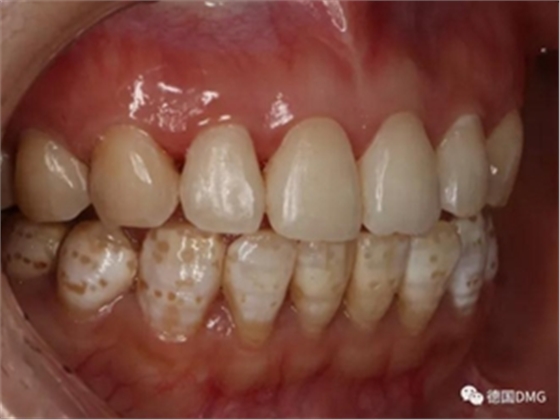

1,術前照片,全口氟斑牙,前牙表面釉質白堊色+黃色斑點+凹坑缺損。

術前正面?zhèn)让嬲掌?/span>